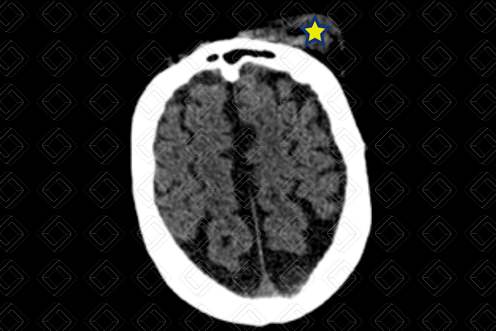

Texto alternativo para a imagem Figura 1. Créditos: Dra. Elazir Mota - Rio de Janeiro/RJ

Descrição da lesão: Tomografia computadorizada de crânio. A umento das partes moles extracranianas na região frontal e periorbitária esquerdas (asteriscos), caracterizando hematoma subgaleal. Não há extensão intracraniana ou sinais de fratura.

Hematoma subgaleal: A umento extracraniano das partes moles, sem extensão intracraniana. Em geral, ocorre por ruptura de veias emissárias que drenam o couro cabeludo, com acúmulo de sangue entre periósteo superficial e aponeurose do músculo do couro cabeludo.